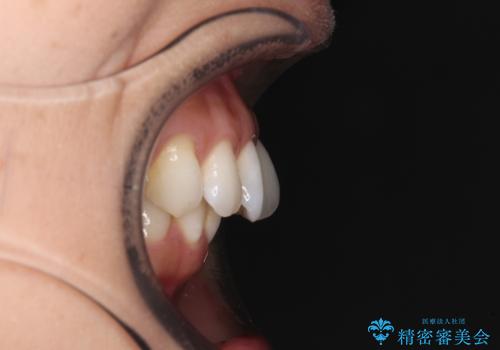

奥歯の噛み合わせをみると、上顎歯列が全体的に前突している状態であり、この咬み合わせのまま歯列を整えると出っ歯になってしまう可能性がありました。

アンカースクリューと補助装置を使用して上顎大臼歯を遠心移動させることで咬み合わせを改善し、ワイヤー装置によりデコボコを解消しながら口元の突出感も改善していくこととしました。